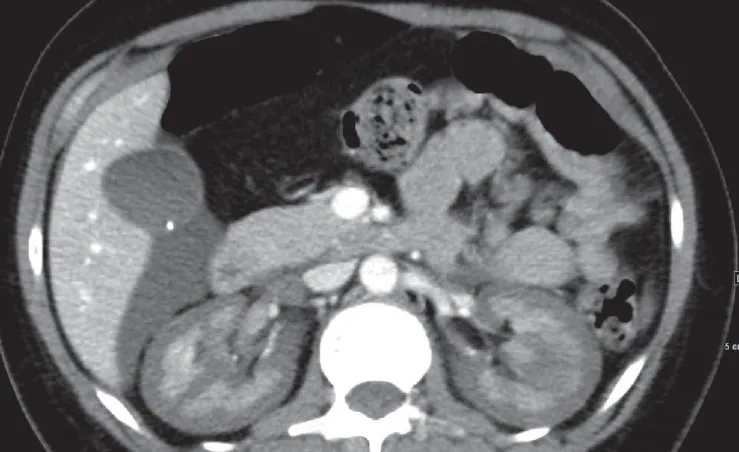

Mais um caso clínico para gravar e aumentar nosso diagnóstico diferencial diante de pacientes com nódulos cutâneos e doença renal

Valkercyo Feitosa

3 anos atrás